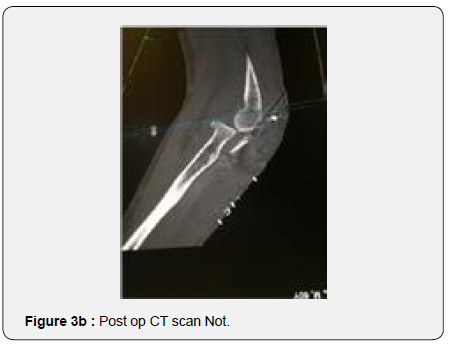

In order to better evaluate the injury and to plan corrective surgery, a CT scan was performed confirming the unreduced comminuted proximal ulna fracture and greater sigmoid notch bone loss with subsequent radio capital subluxation (Figures 3a & 3b) After disussing the case with the patient, decision was made to perform a surgical revision of the osteosynthesis using a tricortical iliac bone graft as the bone gap present seemed to prevent adequate articular stability and bone healing.